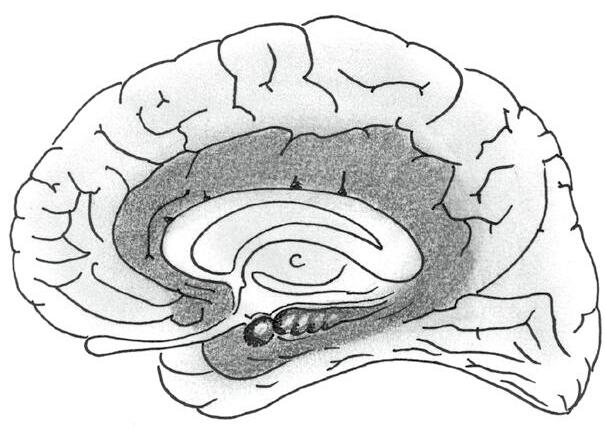

V kontextu koncového mozku je nezbytné zmínit jeden z nejsložitějších systémů mozku, který je spojen zejména s emocemi a pamětí. Označujeme ho jako LIMBICKÝ SYSTÉM. Dostává a zpracovává obrovské množství informací z řady oblastí mozku, smyslových orgánů a celého těla a zpětně ovlivňuje prakticky celý mozek.

• Korové oblasti limbického systému lemují na mediální (vnitřní) ploše koncového mozku kalózní těleso (latinský výraz limbus znamená okraj, lem či límec). Zasahují tak do všech mozkových laloků. Nejmohutnější je cingulární závit (gyrus cinguli), který leží těsně nad zmíněným vazníkem, a parahipokampální závit (gyrus parahippocampalis) na vnitřní ploše spánkového laloku. Do korových oblastí limbického systému řadíme také korové oblasti čichu na spodní straně čelního laloku.

• K podkorovým částem limbického systému patří především amygdala (corpus amygdalae), která se podílí zejména na vyhodnocení situace a přiřazování emočního náboje, a hipokampus (hippocampus), jenž hraje hlavní roli v genezi dlouhodobé paměti. Obě struktury jsou párové, najdeme je v hloubce obou spánkových laloků.

Limbický systém dostává v každém okamžiku obrovské množství informací ze smyslů, z těla i z ostatních částí mozku. Mnohé z těchto vstupujících informací (např. ze smyslů) sem přicházejí přednostně a jsou zpracovávány prioritně. Jelikož je limbický systém spojen s emocemi, lze říci, že emoce mají pro mozek prioritu před ráciem. Jinými slovy, v našem mozku platí nerovnost EMOCE > ROZUM. Při práci s lidmi na to nesmíme zapomínat (a vyplatí se nepomíjet to ani v našich vlastních „neprofesních“ životech a rolích).

cingulární závit

čichový bulbus

čichová korová oblast

Obr. 2.18 Limbický systém

amygdala (v hloubce)

hipokampus (v hloubce)

parahipokampální závit

kalózní těleso